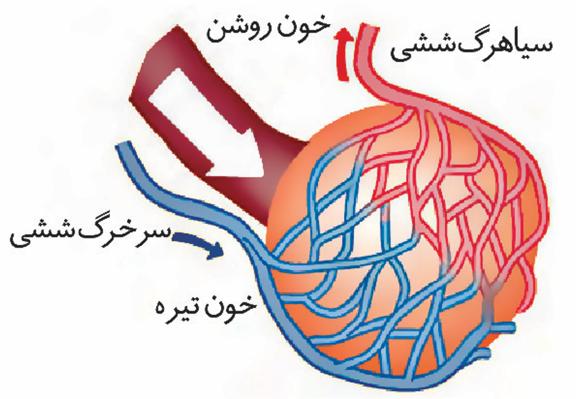

۲-در مویرگهای خونی اطراف حبابکها سرخرگ ورودی به مویرگ خون تیره و سیاهرگ خروجی خون روشن دارد.

۳-مویرگهای آبشش ماهی بین دو سرخرگ قرار دارند. سرخرگ ورودی خون تیره و سرخرگ خروجی دارای خون روشن است.